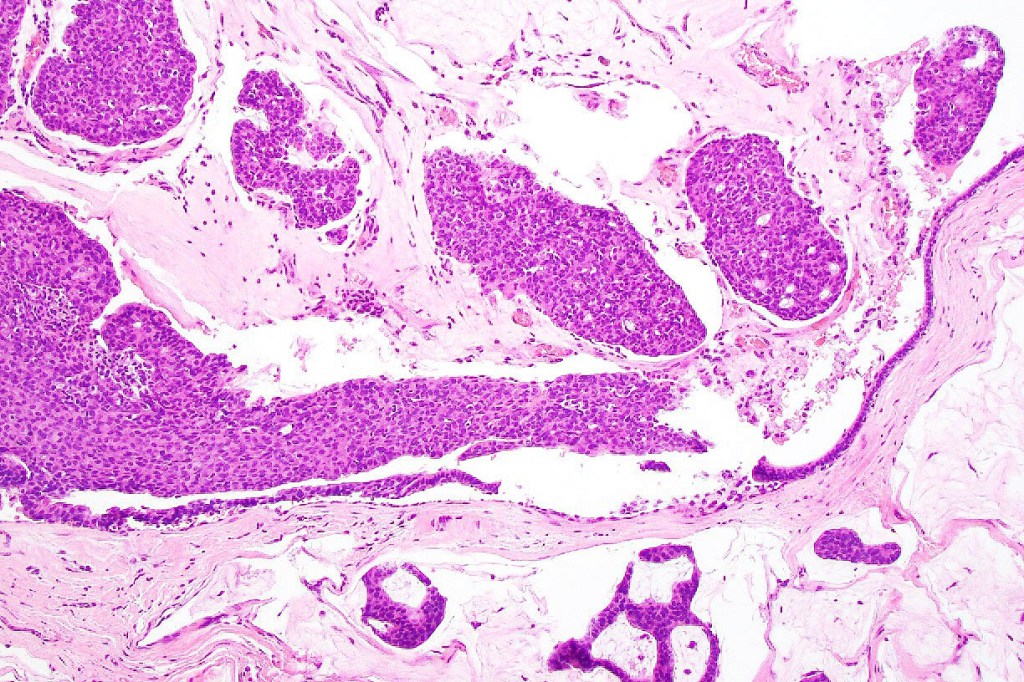

•Mucinous carcinoma is characterized by epithelial islands dispersed in a rich mucinous stroma

•EMPSGCa– multiple nodules of uniform epithelial cells with vesicular nuclei & small nucleoli

•In situ component sometimes evident

•Papillae & cribriform pattern sometimes evident

•+/- invasive mucinous carcinoma (50%)